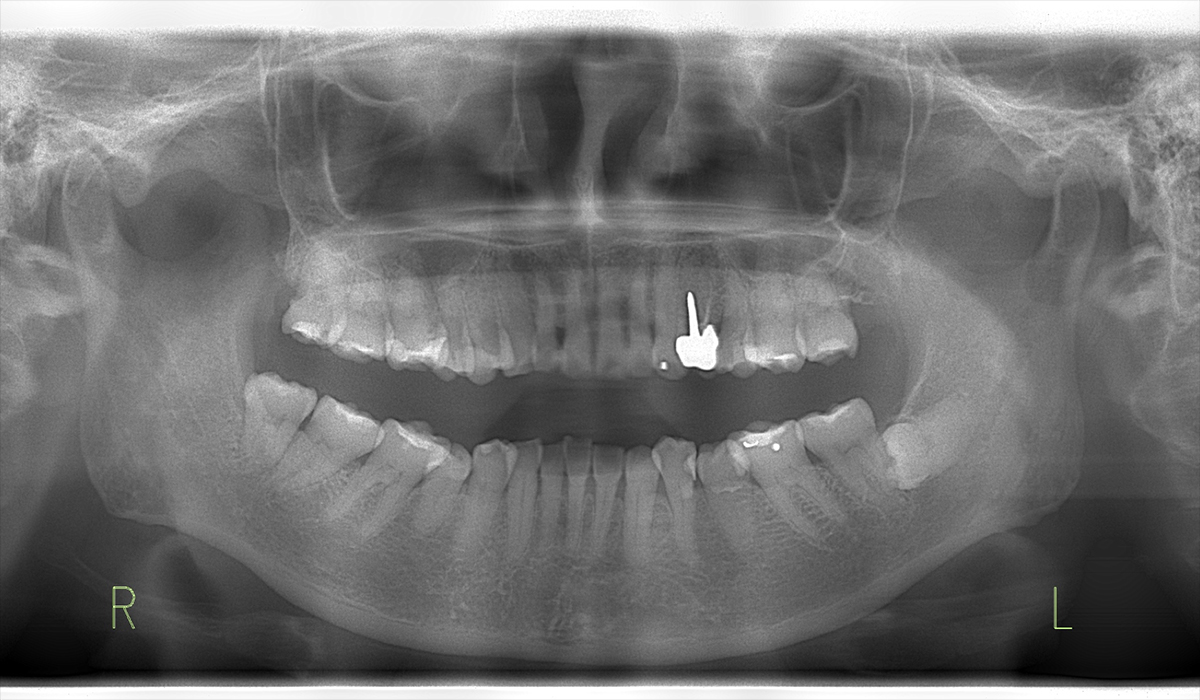

初診時のレントゲン写真

レントゲン写真にて

歯が折れていることを確認

歯が折れていることが、レントゲン上で確認できました。